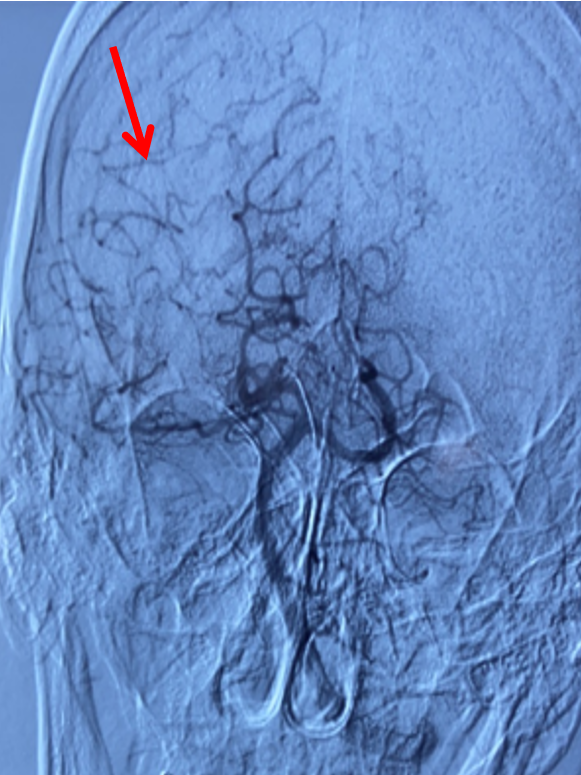

左侧颈总动脉正位造影:双侧大脑前动脉显影,且右侧大脑前动脉通过软膜吻合向右侧大脑中动脉支配区域供血(箭头示)。